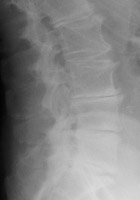

Degenerative disk disease

The presence of a linear radiolucency in the disk space (vacuum phenomenon) is a typical finding of degenerative disk disease. It is often associated to other findings of degenerative disk disease such as disk space narrowing and endplate sclerosis. Gas in the disk space is rarely associated to disk space infection.